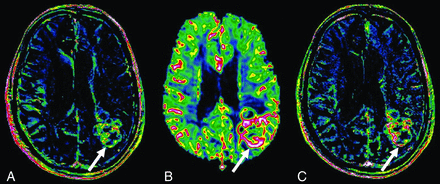

Correlation between the 2 estimates of microvascular density (CBV and VP) is also significant and stronger than that between Ktrans and CBV and Ktrans and VP. Figure 4 shows an area in the posterior aspect of the tumor showing high CBV and VP values but not particularly elevated Ktrans values. Such a low correlation (ρ = 0.382) for 2 parameters, Vp and CBV, which are supposed to provide the same physiologic information (microvessel density), is somewhat surprising. This may be partially explained by slight spatial misregistration as discussed above. Another phenomenon that can account for this low correlation is microscopic hemosiderin deposition, which is known to be present in high-grade gliomas and cause signal loss in T2* sequences. Although areas of blooming and voxels with very low values were excluded, small effects from microscopic hemosiderin would still be present. Another difference inherent in the techniques that could account for the low correlation is blooming on DSC–MR imaging. The T2* approach relies on dephasing of the protons within a voxel caused by the intravascular contrast, but the dephasing effect extends to surrounding voxels as well. T1 shortening caused by intravascular contrast on DCE–MR imaging does not extend to surrounding voxels to the same extent.

Ktrans (A), CBV (B), and Vp (C) maps through the center of a grade IV glioma. The arrow points toward an area in the posterior aspect of the tumor showing high CBV and Vp values but only mildly elevated Ktrans values.